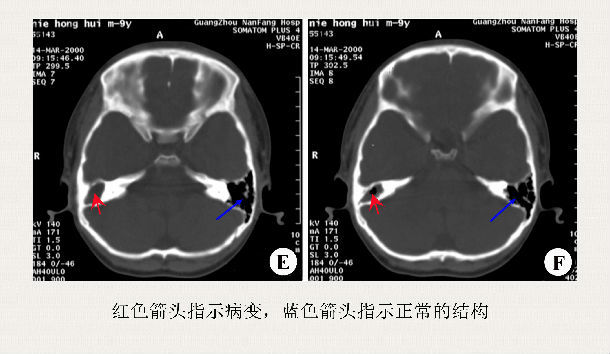

(2)颞骨高分辨率CT扫描:中耳就像一座楼房,有很多个房间,正常情况下这些房间只有空气没有脓液的,CT主要看看有几个房间有病变。